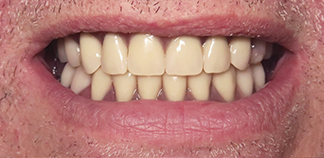

До лечения

Жалобы на отсутствие зубов.

Как лечили

Установлены шесть имплантов на верхней челюсти и четыре импланта на нижней. Зафиксированы постоянные коронки.

Лечащие врачи

МИРОШНИЧЕНКО Алексей Михайлович, БАЛЕВ Дмитрий Олегович